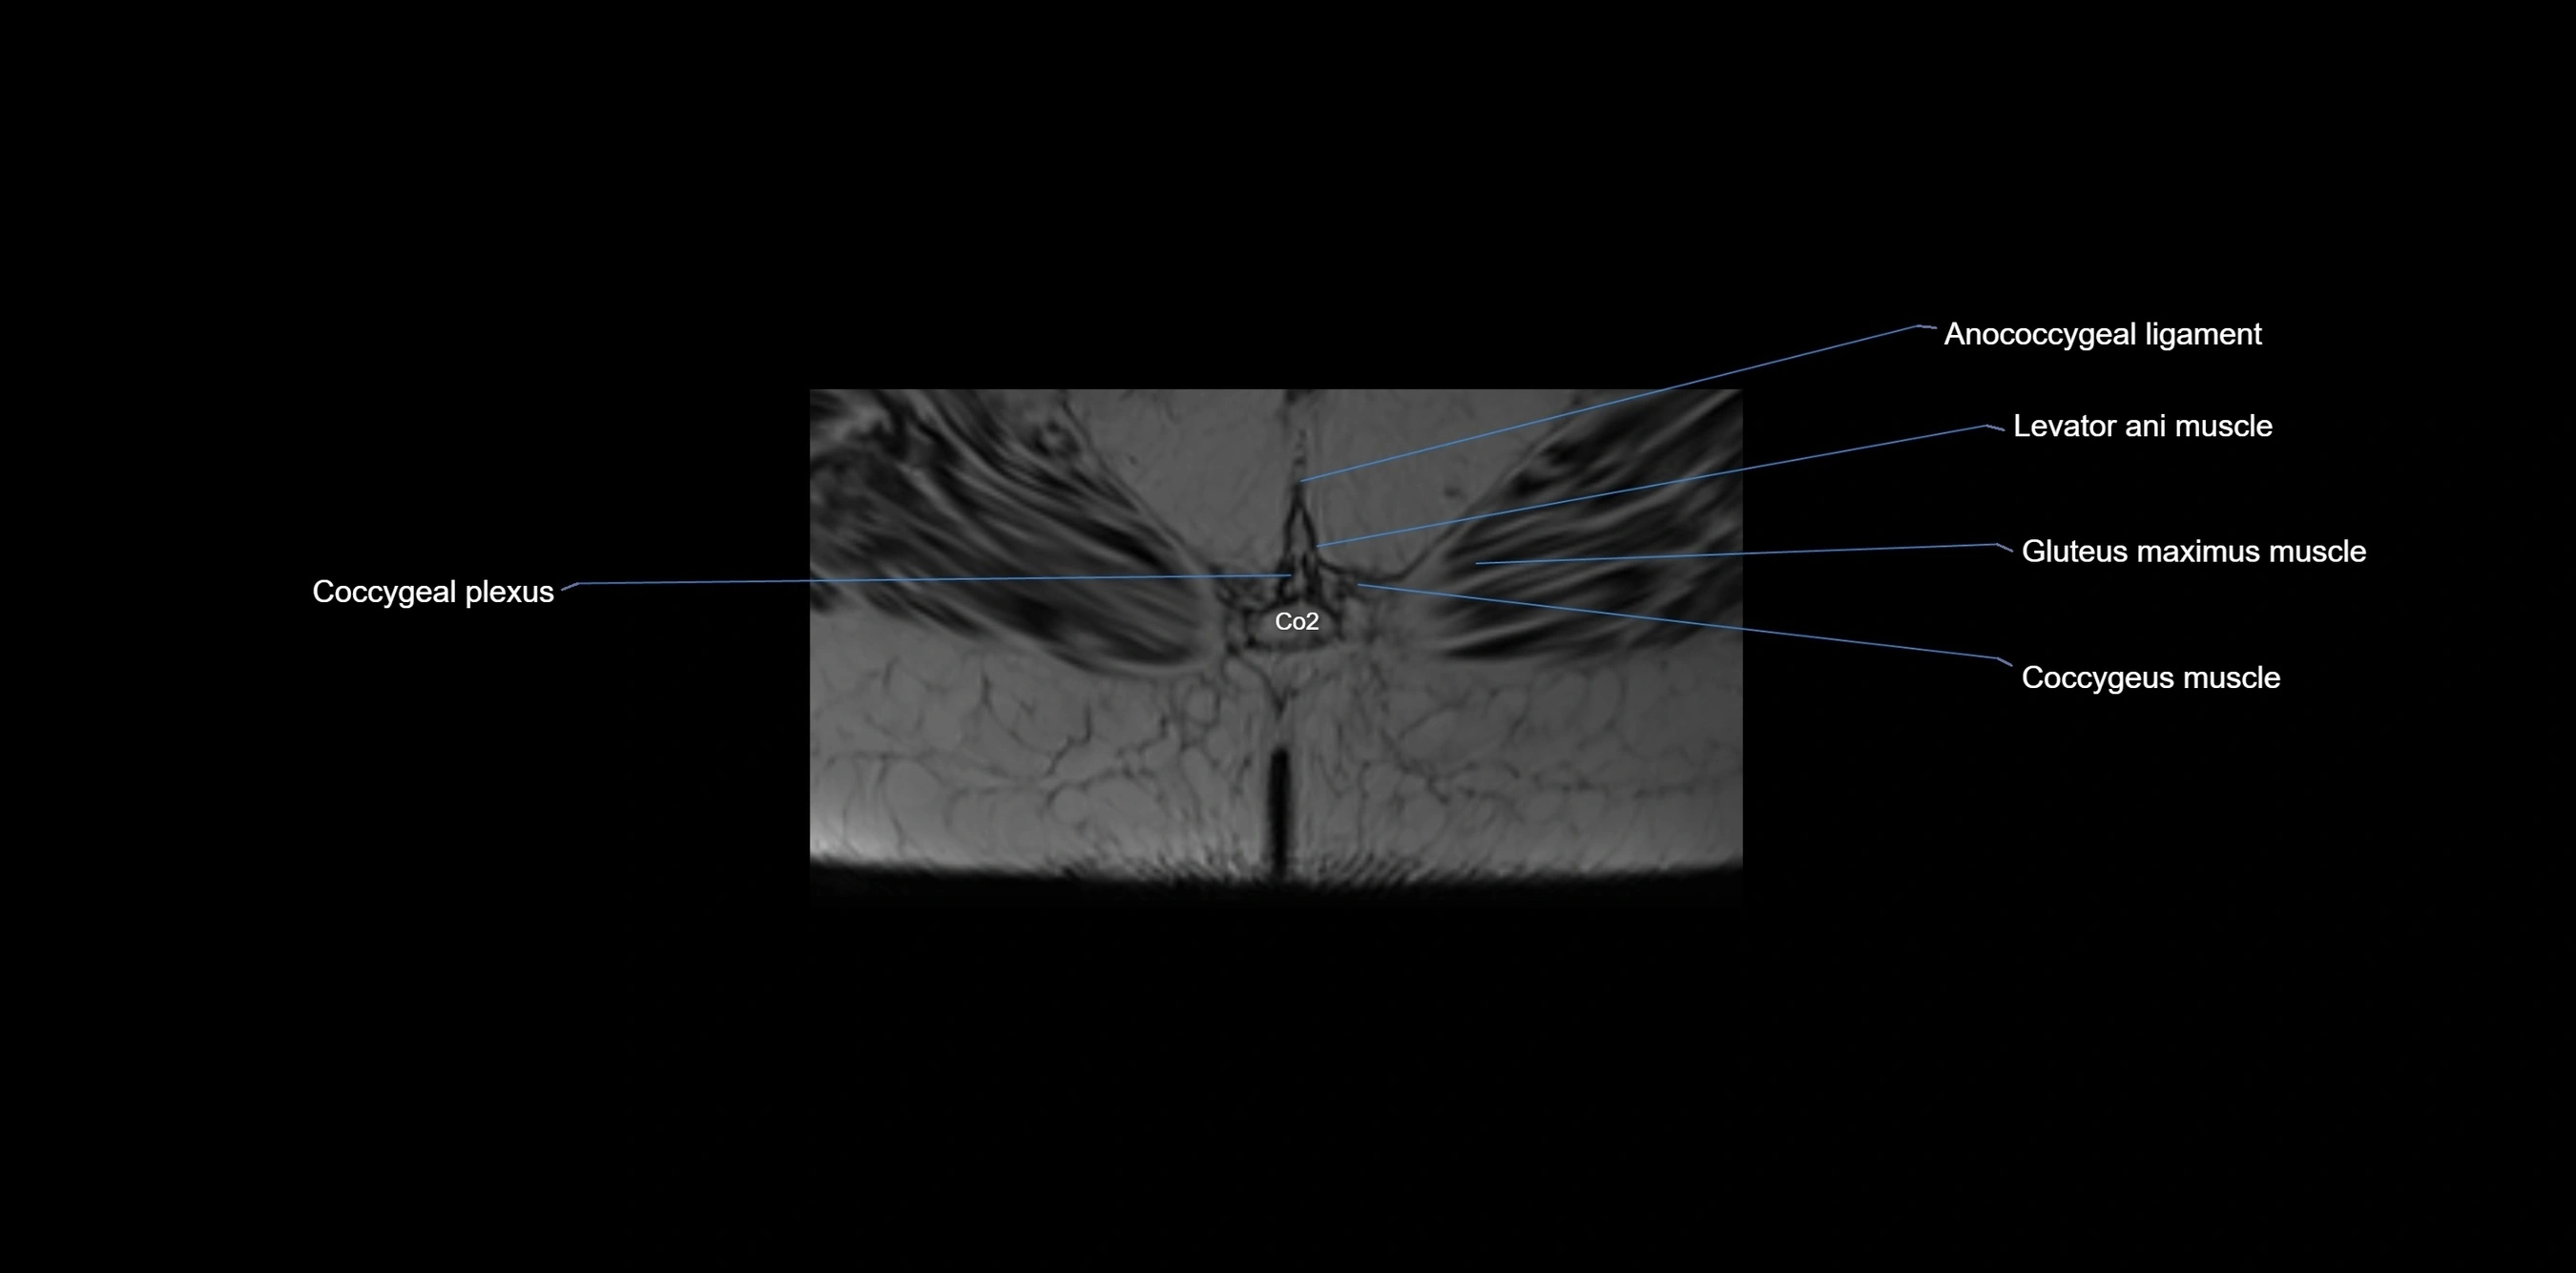

MRI image

image